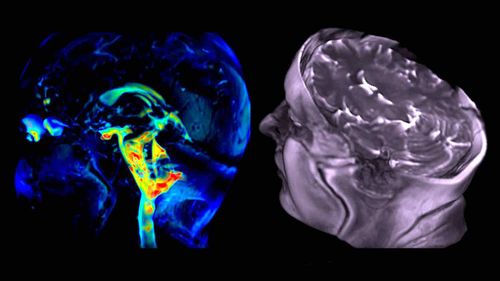

Parkinson, une terrible maladie neurologique dégénérative résultant en la perte progressive de neurones, affecte actuellement environ 160 000 français. À l'heure où de potentiels traitements curatifs sont en cours de développement, il devient d'autant plus important de diagnostiquer la maladie le plus tôt possible. Récemment, des